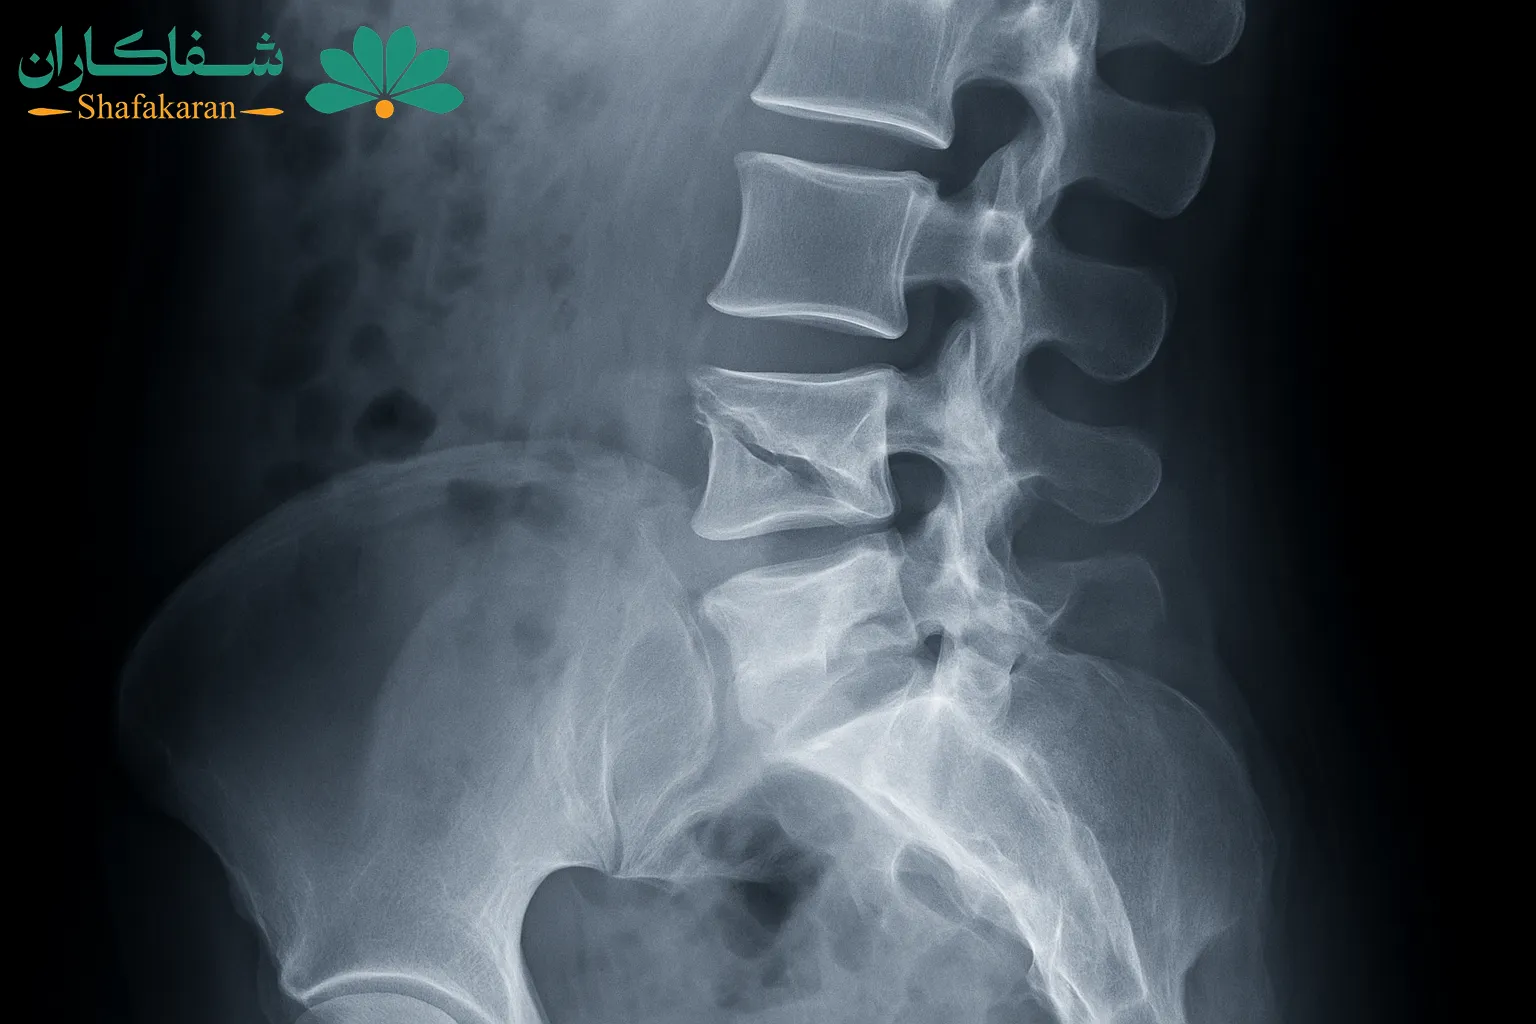

آسیبهای ستون فقرات و دیسک کمر

یکی از علل مهم کمر دردهای خطرناک، آسیبهای ستون فقرات و مشکلات دیسک کمر است. این آسیبها میتوانند ناشی از ضربه، افتادن، یا حتی بلند کردن نادرست اجسام سنگین باشند و در موارد شدید فشار روی عصبها باعث درد شدید و علائم عصبی شوند. شناخت این نوع کمردرد و تشخیص به موقع، اهمیت بالایی در پیشگیری از آسیبهای دائمی دارد.

- فتق دیسک کمر که باعث فشار روی عصبها و درد شدید میشود.

- شکستگی مهرهها به دلیل ضربه یا پوکی استخوان

- تنگی کانال نخاع که منجر به فشار عصبی و ضعف عضلانی میشود.

- آسیبهای ناشی از حرکات نادرست یا بلند کردن اجسام سنگین